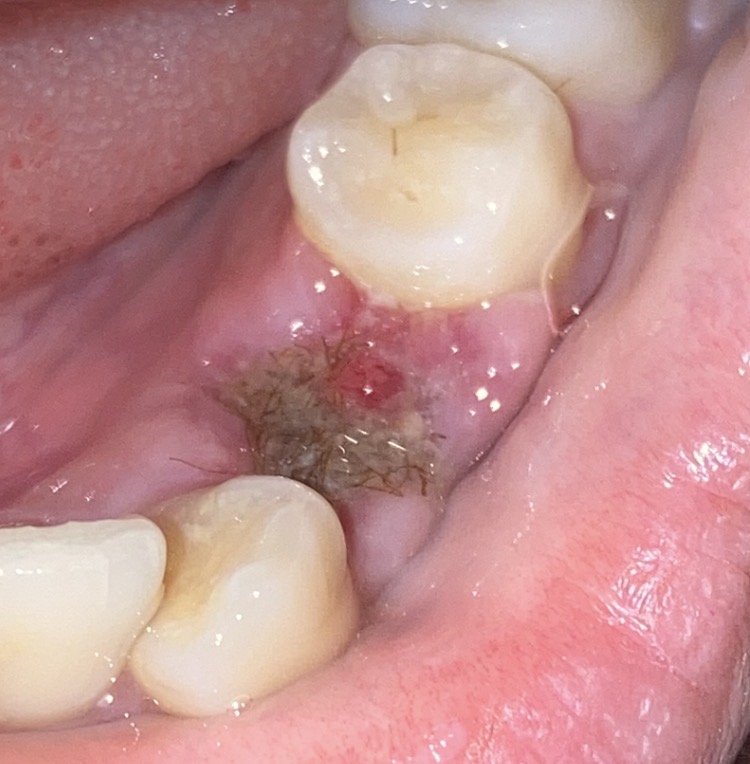

เมื่อวานไปใส่ยา บอกหมอว่าไม่ปวดแผลแล้วแต่รู้สึกปวด ๆ แถวเหงือก หมอก็ไม่ว่าอะไร พอกลับบ้านมายาดันหลุด แล้วเห็นตุ่มแดง ๆ เล็ก ๆ (รูป 2 ) นึกว่าเหงือก